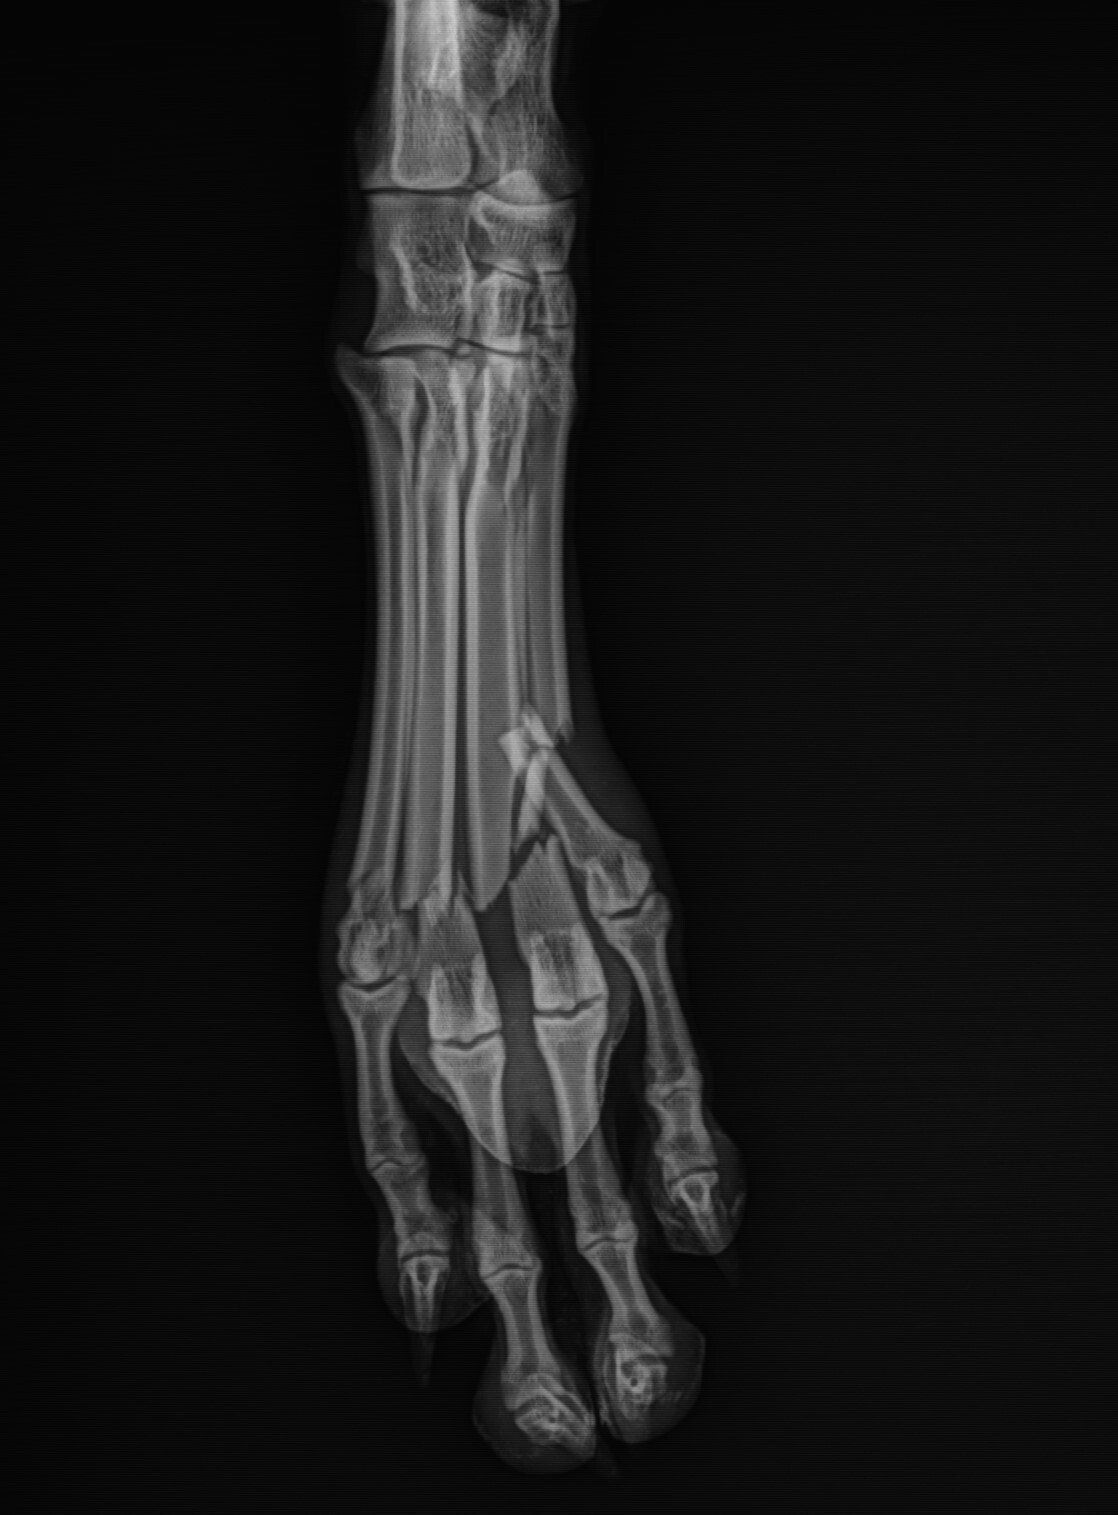

Leg fractures are one of the most common orthopedic problems presented at our clinic and usually result from a traumatic mishap. They can be treated in a variety of ways depending on the location and type of fracture. We can apply a cast to treat certain fractures; however, many fractures will require surgical intervention:

- “Pinning” stabilizes the fracture by inserting a long stainless steel rod into the middle of the bone across the fractured area.

Below are x-rays of just a few orthopedic surgeries before and after that Dr. Gose has performed.